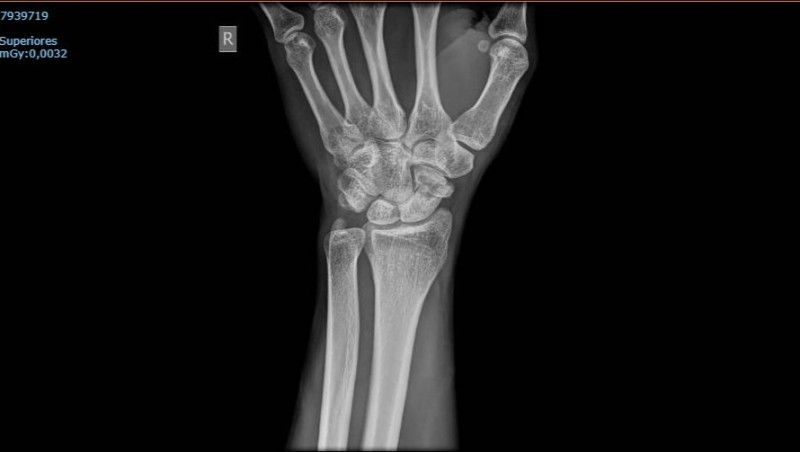

FRACTURA DE ESCAFOIDES CON NECROSIS Hola, tengo un amigo que hace ya 1 año y 7 meses sufrió un accidente en su bicicleta el cual le ocasionó una fractura en la muñeca derecha, específicamente en el hueso escafoides, este hueso conecta el dedo pulgar con el resto de los huesos que se alojan en esa parte de la mano. Después una malapraxis, muchas visitas al médico y muchas más al especialista el proceso hoy en día se encuentra inconcluso, al punto donde me veo en la gran necesidad de solicitar de su ayuda para recolectar el dinero necesario para poder costear los gastos de un especialista privado y le puedan realizar la operación de su mano, no puede esperar mas tiempo porque perdería la movilidad de la mano o podría perder incluso la misma mano debido a la necrosis. El diagnostico presentado actualmente en su mano es: FRACTURA DE ESCAFOIDES CON NECROSIS Esta fractura le ha cambiado la vida ya que desde el primer día hasta el día de hoy el dolor no se ha ido, la vida se le ha vuelto más difícil ya que los movimientos de la mano derecha son limitados y conforme va pasando el tiempo el recuperar el completo movimiento de la mano se ve más comprometido, es por esto que cada día que pasa es peor. Mi nombre es leidy y solo quiero poder ayudarlo, es un gran amigo y no quiero que por culpa de un mal sistema de salud el tenga que pagar las consecuencias teniendo que cambiar por completo su estilo de vida.